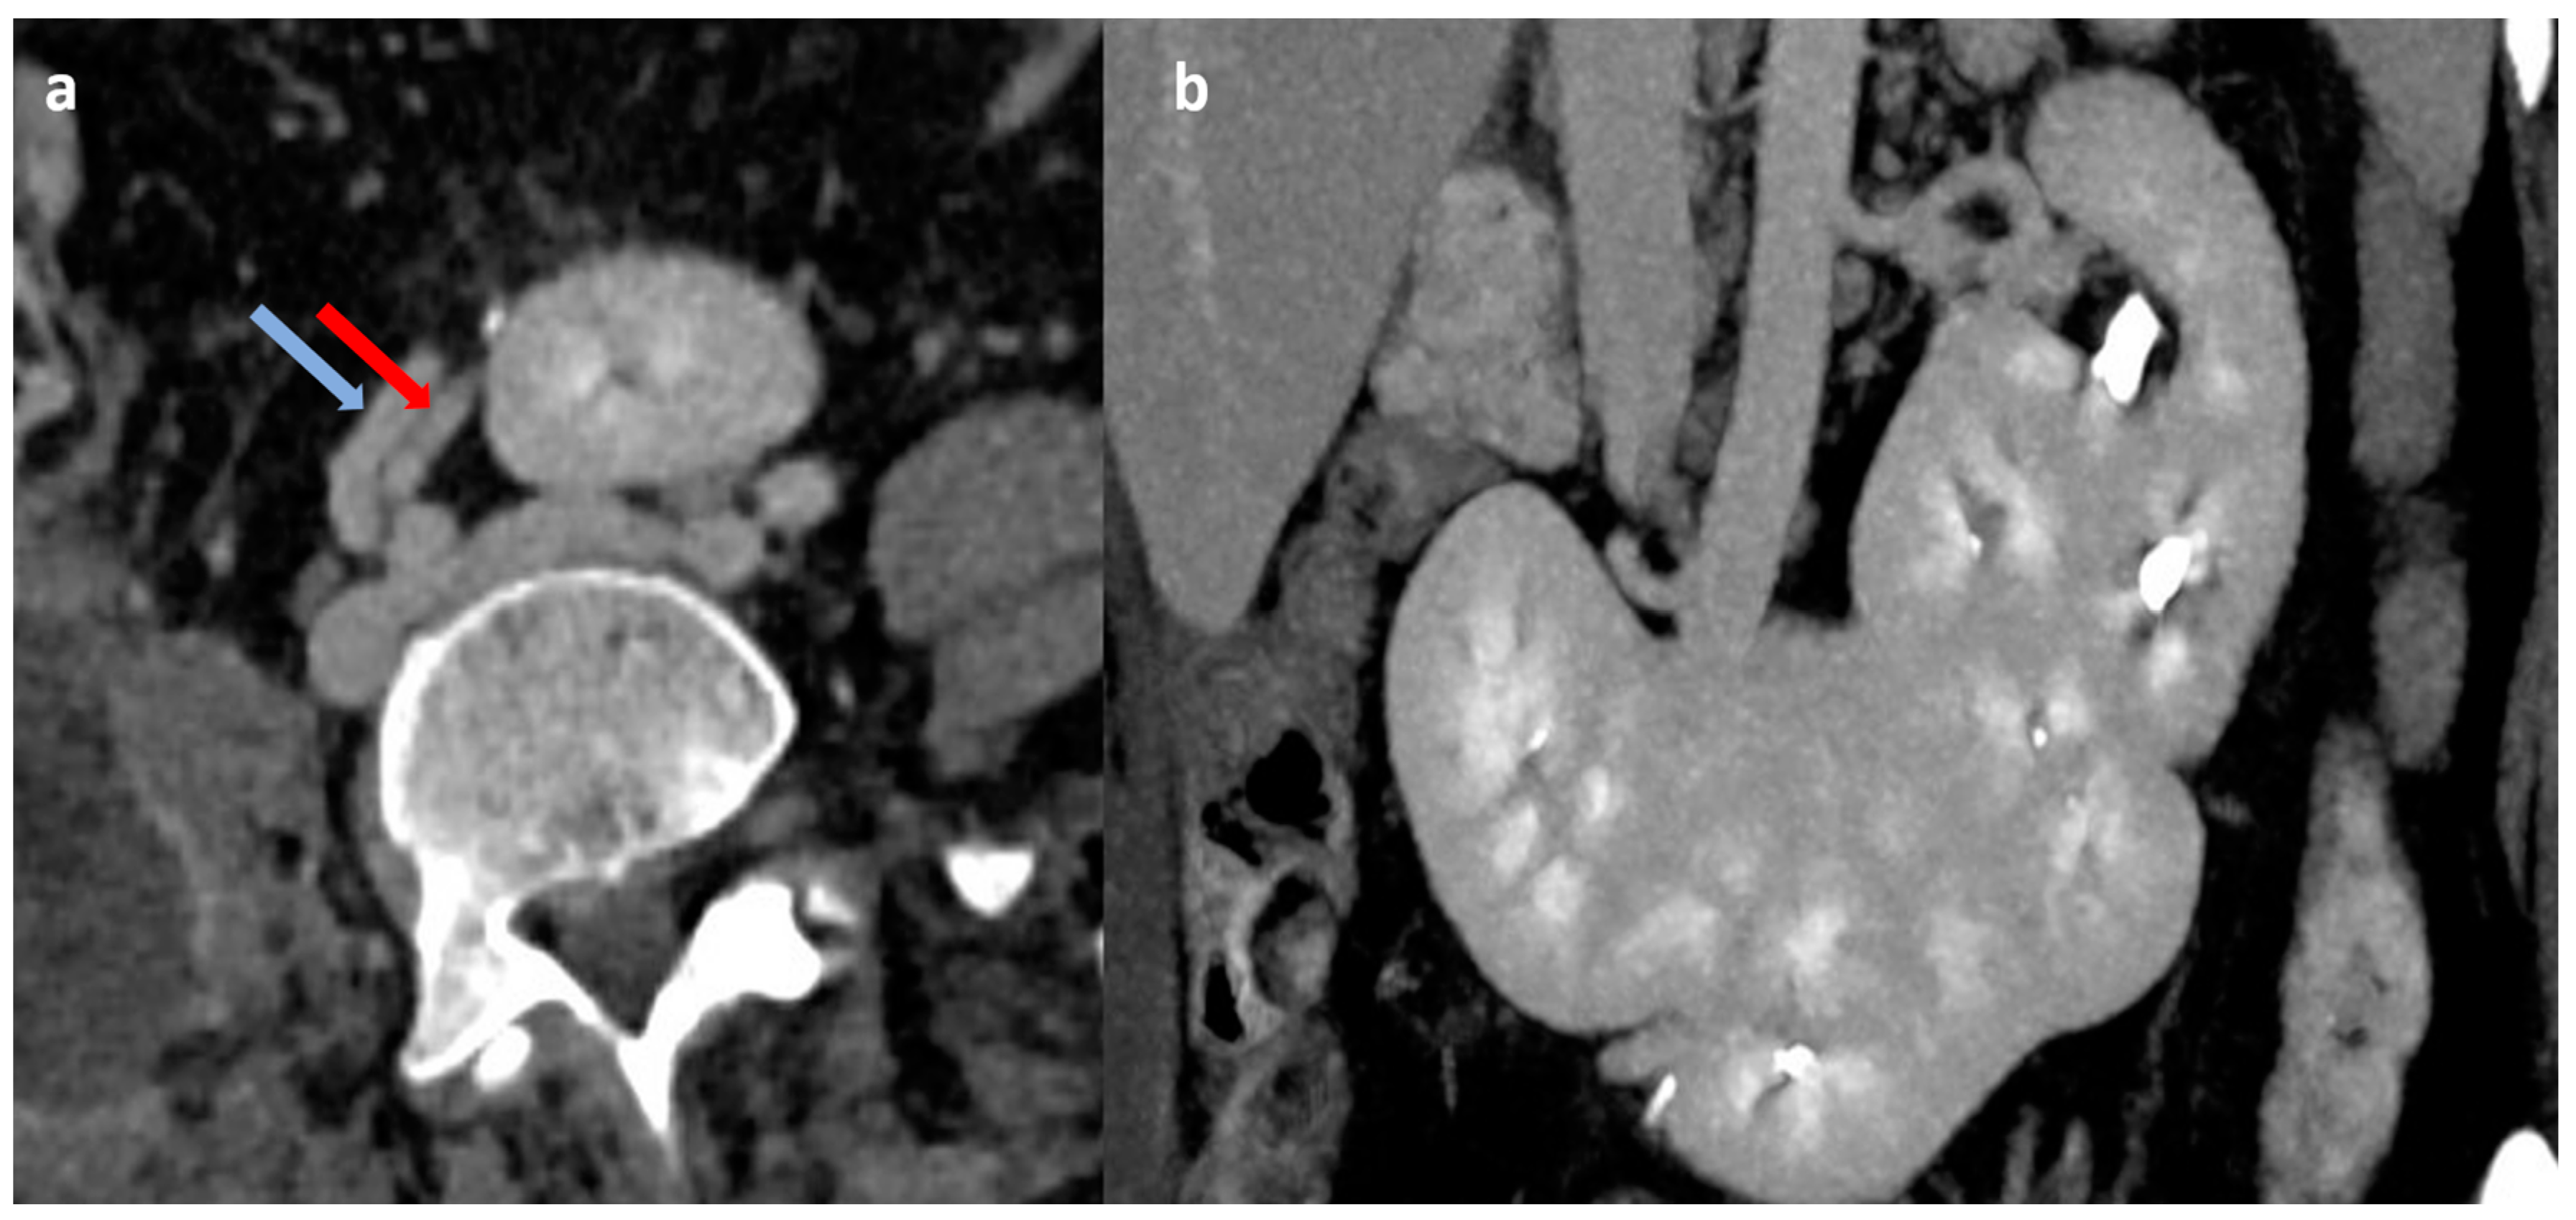

A female in her mid-40s presented to the emergency department with acute onset umbilical pain associated with vomiting. There was no flank pain, hematuria, dysuria, or fever. An ultrasound of the abdomen and pelvis was performed, which showed an empty right renal fossa and fused, conglomerated reniform-shaped structure in the midline at the umbilical region with vascularity noted on Doppler imaging. The patient was further advised on a cross-sectional study for better characterization. A contrast-enhanced computed tomography (CT) study of the abdomen with CT urography was performed, which showed empty right renal fossa and ectopic right kidney in the midline, which was fused with another kidney unit, which was further fused with the lower pole of the left kidney. In contrast sequences, the supernumerary kidney was receiving blood supply from the right common iliac artery and draining through the right common iliac vein, and both right and left kidneys had a normal vascular supply from the aorta and inferior vena cava (Figure 1). On delayed images, both the right ectopic kidney and left kidney showed a bifid pelvicalyceal system, and the supernumerary kidney showed a single pelvicalyceal system, with a total of five pelvicalyceal systems present in our patient (Figure 2). The patient was managed conservatively and became asymptomatic after 2 days.

Figure 1. Contrast-enhanced CT abdomen images (a) in axial plane showing the vascular supply of transversely oriented supernumerary kidney unit from right common iliac artery (red arrow) and vein (blue arrow); (b) in coronal plane showing triple fused supernumerary kidneys.